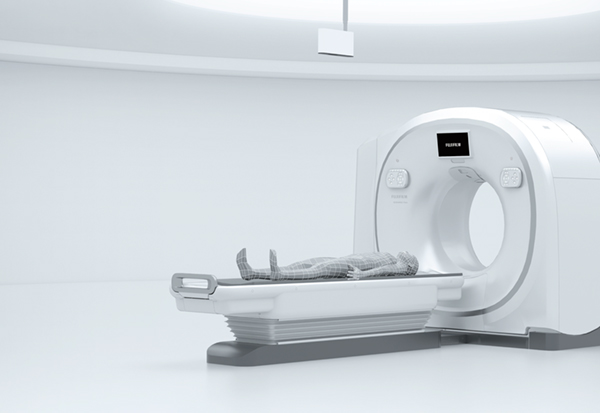

SCENARIA View(シナリア ビュー)

富士フイルムヘルスケア

CT 64列/128スライス

進化したから見える,新しい世界をあなたに。

SCENARIA Viewでまだ見ぬ世界へ。

広々とした800mm開口径と200mm横スライド寝台

ガントリ開口径:800mmφ